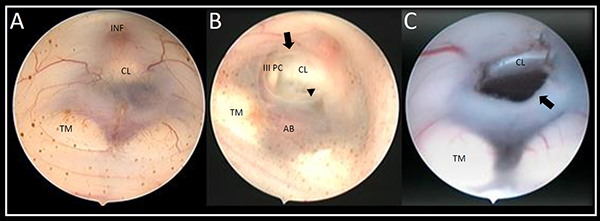

Como hallazgo intraquirúrgico, en 8 casos (62%) se constató el cierre completo de la ostomía, en 4 (30%) se observó el cierre de la ostomía por aracnoiditis, mientras que solo en 1 caso (7%) la ostomía permanecía permeable (Figura 2).

Figura 2. Imágenes intraquirúrgicas del piso del tercer ventrículo, donde se observan los hallazgos durante la Re-TVE. A) Ostomía cerrada íntegramente, no se observan rastros de la primera TVE, B) Ostomía cerrada con aracnoiditis, es posible observar los bordes libres de la ostomía (flecha) y la aracnoiditis en su interior (punta de flecha), C), ostomía permeable, se aprecian los bordes libres de la ostomía (fecha). III PC: tercer par craneal, AB: arteria basilar, CL: clivus, INF: infundíbulo, TM: tubérculos mamilares.

Durante la revisión endoscópica, los posibles hallazgos quirúrgicos en relación a la TVE son: 1) ostoma cerrado completamente, 2) ostoma cerrado por la presencia de aracnoiditis o 3) ostoma permeable.17,20,22,23 En el estudio multicéntrico publicado por Breimer et al. observaron una mayor tasa de éxito en aquellos pacientes que durante la Re-TVE la ostomía se encontró completamente cerrada. Mientras que aquellos pacientes en los que hallaron aracnoiditis en la cisterna presentaron una mayor tendencia a requerir un sistema de derivación dentro de los 6 meses.2 Siomin et al. presentó 20 pacientes, en todos los casos el ostoma se encontró completa o parcialmente cerrado, mientras que Koch y compañía en su serie de 12 casos, describieron 9 pacientes con ostoma totalmente cerrado y 3 en quienes presentaban una membrana aracnoidea.15,25 Al igual que lo expuesto en la bibliografía, de los 13 casos presentados en nuestro trabajo, 8 presentaron el cierre completo de la ostomía, 4 aracnoiditis y 1 solo caso de ostomía permeable.